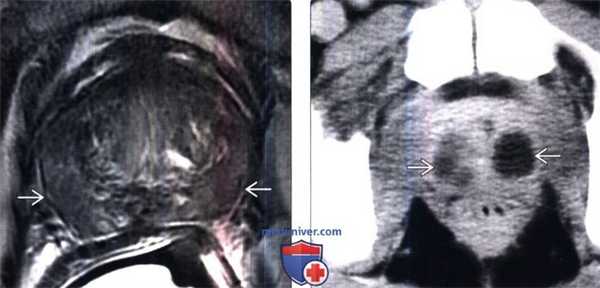

(Слева) Аксиальный срез Т2-ВИ: низкоинтенсивный сигнал периферической зоны у пациента с простатитом. Если воспалительный процесс охватывает периферию железы фокально, для дифференцирования с раком может потребоваться биопсия.

(Справа) КТ с контрастированием, аксиальный срез: множественные гиподенсные участки с усилением сигнала по периферии, соответствующие абсцессам. Медикаментозной терапии обычно достаточно, но иногда может потребоваться дренирование абсцесса.